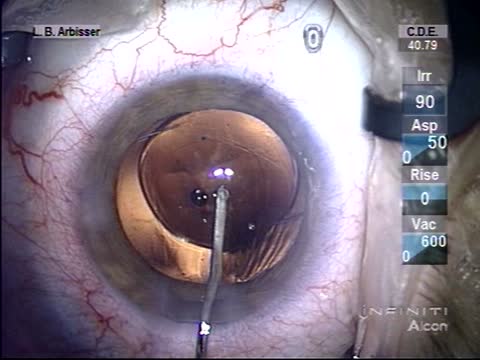

Residual Nuclear Fragment

Lisa Brothers Arbisser, MD